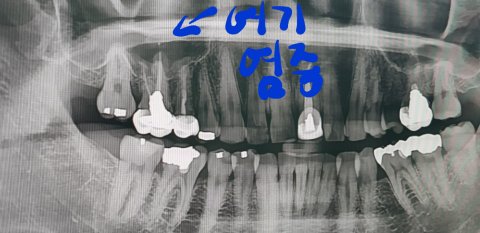

치아 위에 예전 치료하다 생긴 염증으로 인해 농이 찬거라서 바로 치아 발치 후 임플란트나 브릿지를 해야한다 하셨어요

여기에 염증 있어서 조금만한 점인데 신경치료나 마취치료등 잘못으로 인한거라던데 언제 한건지 아냐하셔서 모른다 하니 무조건 뽑아야한다셨어요

문제는 저 염증으로 인해 농이 가득하다는데 무조껀 이건

어금니 치아를 발치 해야한다하더라구요 다른 방법은 없구요 이비인후과에 갈 필요도 없고

다음날 치아 발치후 ct사진이구요